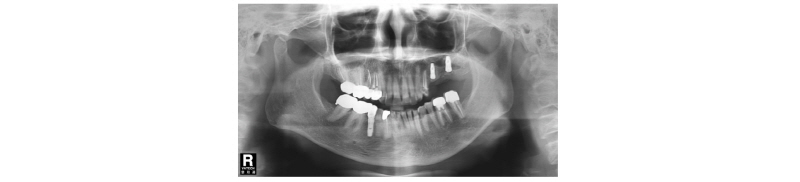

70세의 여자환자로 상악에 사용하던 부분틀니가 불편하다고 호소하시며 내원하였다. 부분 틀니의 지대치인 상악 좌측 견치 또한 보철물 하방으로 우식이 진행되어 보철물 제거후 우식치료 후 보철물을 재제작하여 장착하기로 계획하였다. 치아가 결손되어 있던 상악 좌측 소구치와 대구치 부위는 임플란트 식립(#24i-26i, 27i)을 통한 고정성 보철물 수복을 계획하였다(Fig. 19). 장기간의 부분틀니 장착으로 인해 임플란트 식립 예정 부위의 심한 치조제 흡수가 관찰되었으며 특히 소구치 부위가 가장 흡수 정도가 심하였다(Fig. 20). 전층판막 형성 후 상악 좌측 제 1 소구치 부위는 치조정에서 약 2 mm 정도의 매우 좁은 치조제 폭경이 확인되었다(Fig. 21). 먼저 상악 좌측 제 1 소구치 부위 치조정에 horizontal intraosseous groove를 작게 형성한 후 협측골에 근, 원심 양측에 vertical intraosseous groove를 형성하였다(Fig. 22). Chisel을 이용하여 협측 골판을 조금 확장시킨 다음 spreader drill (RS kit, Dentium, Korea)을 단계적으로 이용하여 충분히 확장시켜 임플란트 식립을 위한 공간을 확보하였다(Fig. 23). 분리된 협,설측 골판 사이 공간으로 Ø4.3 × 10 mm (Implantium, Dentium, Korea) 임플란트를 식립하였다(Fig. 24). 상악 좌측 대구치 부위는 상악동 거상술(측방접근법)을 시행하여 #26i, 27i : Ø4.3 × 10 mm, Ø4.8 × 10 mm (Implantium, Dentium, Korea)를 식립하였다(Fig. 25). 식립된 24i 임플란트와 협,설측 골판 사이의 gap에 합성골 (Osteon II, Xenoss, Korea)을 적용한 다음 협측 골판 상방에 콜라겐함유 합성골(Osteon II Collagen, Xenoss, Korea)을 추가적으로 적용하였고 식립된 26i, 27i 임플란트 부위의 협측골 두께가 얇아서 협측골 상방에도 콜라겐함유 합성골(Osteon II Collagen, Xenoss, Korea)을 적용하였다(Fig. 26). 골이식재 상방에 흡수성 교원질 차폐막(Collagen, Xenoss, Korea)을 피개한 후 감장절개를 통해 장력없이 봉합하였다(Fig. 27, 28). 약 10일 후 발사 시의 임상소견으로 정상적으로 치유가 잘 진행되었다(Fig. 29). 술 후 파노라마 방사선 소견으로 치조제 분할술을 통해 식립된 24i 임플란트와 상악동 거상술(측방접근법)을 시행하여 식립된 26i, 27i 임플란트가 확인되었다(Fig. 30). 4개월 치유 후 이차 수술 시 전층 판막거상 후 협측으로 충분히 증가된 치조제 폭경과 식립된 임플란트 주위에 이식한 골이 혼화되어 치유된 양상이 확인되었고 치유지대주를 연결하였다(Fig. 31). 이차 수술 후 치유가 정상적으로 진행되어 통법에 따라 보철 수복하였다. 보철물 수복 직후 방사선 사진 소견으로 식립된 24i 임플란트의 변연골 위치가 확인되었다(Fig. 32). 보철물 장착 후 1년 후 방사선 소견에서 임플란트 주위 변연골이 안정적으로 잘 유지되고 있었다(Fig. 33). 보철물 장착 4년 후 follow- up 결과 임플란트 주위 치은이 약간 퇴축된 양상을 보였으나 임상적으로 특이한 소견이 관찰되지 않았고 방사선 소견에서 임플란트 주위 변연골이 안정적으로 잘 유지되고 있음을 확인하였다(Fig. 34-36).

Fig. 19. First visit. Panoramic x-ray view. |